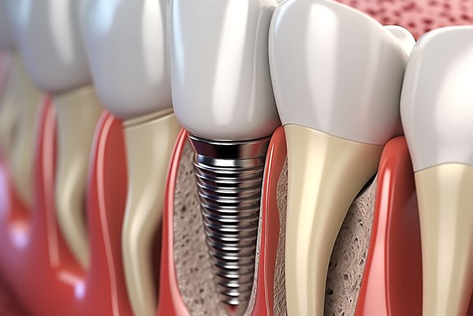

¡Sí! La Dra. Carolina Gómez ofrece implantes dentales tanto para dientes individuales como para arcada completa, utilizando tecnología avanzada para mayor precisión y comodidad. Ya sea que le falten uno o varios dientes, le ayudaremos a restaurar la funcionalidad y la belleza de su sonrisa.